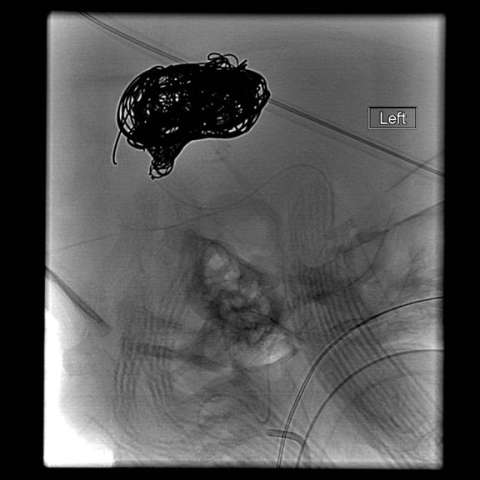

Endovascular embolization is the preferred method of treatment. In an embolization, the abnormal blood vessels are intentionally closed with soft platinum coils or liquid embolic agents, which reduce the abnormal blood flow to the vein of Galen. Sometimes, several procedures are required over a period of several months.